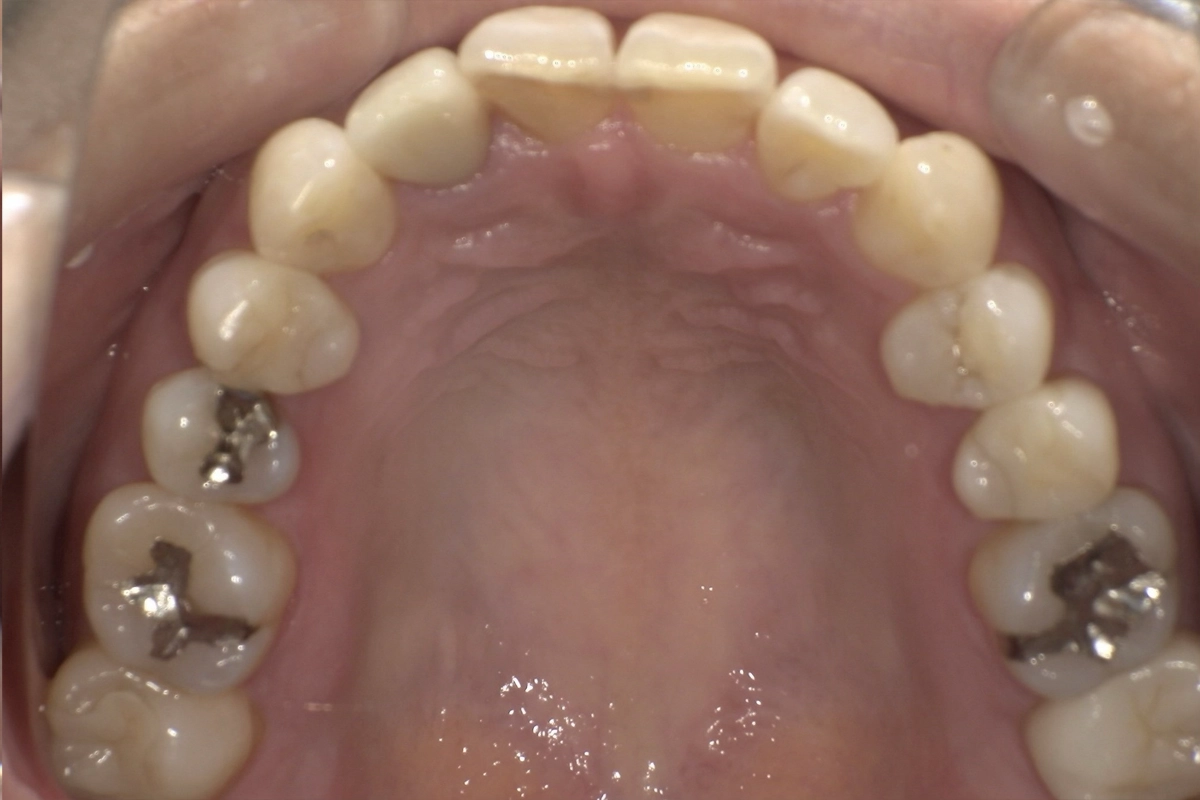

上の前歯にも軽度の乱れがあり、左右の側切歯から犬歯にかけて歯列のアーチが崩れていました。

今回は、上下ともに前から5番目の歯(第二小臼歯)までを対象範囲として治療を行いました。

奥歯(6番目以降の大臼歯)は動かさず、前歯から小臼歯までの範囲に集中してマウスピースで歯を移動させる計画です。

重なり合っていた上下の前歯がきれいに配列され、滑らかなアーチを描く歯並びになりました

歯の重なりが解消されたことで、歯ブラシやフロスが隅々まで届きやすくなりました。

治療前に見られた歯石の沈着しやすい環境が改善され、虫歯や歯周病の予防がしやすい状態になっています。